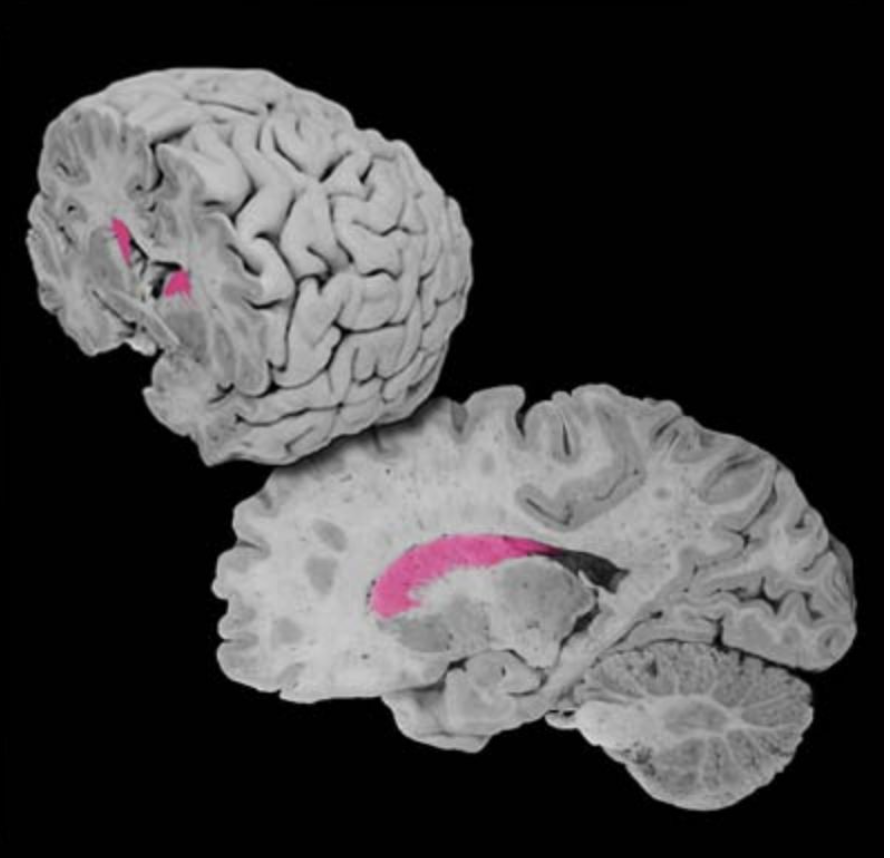

Optic radiations

Well-defined fiber bundles in the subcortical white matter of the parietal, temporal, and occipital lobes that contain the axons of lateral geniculate neurons, which carry visual information to the primary visual cortex (Brodmann's area 17); the temporal portion of these bundles that loop around the inferior horn of the lateral ventricle is known as "Meyer's loop."